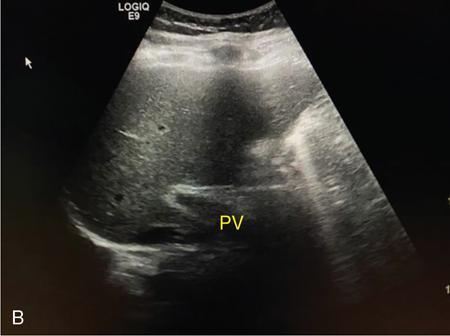

Samarjit Ghuman, Seema Sud, Deeksha Rastogi, Swapnil Sheth, T.B.S. Buxi PLAIN RADIOGRAPHY FOR HEPATOBILIARY IMAGING The diagnostic imaging techniques for hepatobiliary imaging can be intimidating with many techniques/modalities providing the information desired. The job of the diagnostic radiologist includes being familiar with the available choices and pick the ‘best fit’ keeping in mind the pros and cons of each modality, which includes plain X rays, Contrast studies using plain X rays and fluoroscopy, Ultrasound includiojng Doppler and Ultrasound elsastography, CT including multiphase CT and MRI and MRI elastography. Understanding the strengths and weaknesses of every modality as well as the ability to tailor each study individually will help to optimise patient cares. The abdominal radiograph is performed almost exclusively in the supine position and in the AP (anteroposterior) projection. In case of acute abdomen, an erect chest radiograph should also be performed to look for free air under the diaphragm. The standard abdominal radiograph should extend from the diaphragm to the inferior pubic rami, and includes the lateral abdominal wall musculature. Routinely no preparation is required for abdomen radiograph done for hepatobiliary imaging. The radiograph has limited soft-tissue contrast, however, the liver being the largest intra-abdominal organ, casts a perceptible shadow. The margins of the liver can indirectly be seen by outline of adjacent organs like lung, hemidiaphragm, pro-peritoneal fat line, kidney and gas shadows of stomach/colon. The right lobe is seen better than the left lobe of liver. The following pathologies may be visualized on the plain radiograph of the liver. Liver enlargement Liver mass Calcification Increased radiodensity of the liver Decreased radiodensity of the liver An ultrasound is the first line investigation; however, a radiograph may be done for routine evaluation of abdominal pain. The following pathologies may be seen on plain radiograph of the biliary tree. Calculi and Calcifications Gas ULTRASOUND OF HEPATOBILIARY SYSTEM Ultrasonography (USG) is the initial imaging modality of choice for scanning hepatobiliary system. USG is accurate and has high sensitivity and specificity in diagnosing biliary pathologies. Table 9.1.1 shows indications of ultrasound in hepatobiliary system. The real-time nature of ultrasound lends itself to demonstrate mobility of calculi and sludge and the sonographic Murphy sign can easily be elicited during scanning. The main disadvantage is operator dependence, patient’s body habitus, presence of gas which can obscure the visualization of organs, overlying bandages in a postoperative patient and incomplete evaluation in a nonfasting state. USG of upper abdomen should be done after 6–8 hours of overnight fasting. Milk and fatty food should be avoided as they cause contraction of the GB and may cause the GB walls to appear thickened. History of previous surgery, especially cholecystectomy should be elicited. The patient may be positioned in supine or left lateral decubitus position. The GB can be scanned from a high/lateral view, looking through the ribs in supine position or through a sub-costal view in left lateral decubitus position. Position of patient may be changed to demonstrate mobility of structures. The GB is an anechoic structure which is located in the GB fossa along the posterior and inferior aspect of the liver. It has a fundus, body and a neck. It should always be examined in at least two planes (Fig. 9.1.6A and B). The wall of the normal GB should measure 3 mm or less and pathological GB wall thickening can be due to cholecystitis or a neoplastic aetiology. Calculi appear as mobile hyperechoic foci, with distal acoustic shadowing. Other pathologies include polyps and sludge which can be differentiated on the basis of their mobility. The CBD measures less than 6 mm in diameter with increase in the diameter with patient’s age and after cholecystectomy. The CBD is usually scanned in an oblique subcostal plane with the patient in the left decubitus position (Fig. 9.1.7). Dilatation of the intrahepatic biliary radicles is readily assessed with USG and normal intrahepatic biliary radicles are usually not appreciated on USG. Ultrasound of the liver, broadly, is done to assess the size, surface (smooth, coarse or lobulated) parenchymal echogenicity (increased or decreased) vascularity and for presence and evaluation of intrahepatic masses or fluid collections. The liver is divided into right and left lobes by plane of middle hepatic vein which passes through GB fossa and notch of IVC (Cantlie Line). Couinauds classification is the most commonly used system for liver segmental anatomy and described liver into eight functional segments. It is based on distribution of portal and hepatic veins. Every segment has its branch from portal vein, hepatic artery and bile duct (Fig. 9.1.8). Curvilinear transducer (3–5 MHz) is used for routine examination of liver and GB (Fig. 9.1.9). A high-frequency linear transducer (9–11 MHz) (Fig. 9.1.10) can be used to look for subtle irregularity of the liver surface for early Cirrhosis and fine details of GB wall. The liver is scanned in deep inspiration, which causes inferior movement of liver, so that superior borders of the liver are well visualized. Supine position is used for the size of the liver. The measurement is made in sagittal mid clavicular position on right side, in craniocaudal dimension. It is taken from diaphragm to the lower end of the liver. It should be <16 cm and varies with age and sex. The liver is divided into four vertical sectors by three hepatic veins and plane of bifurcation of portal vein divides these 4 sectors in to 8 segments. The right hepatic vein creates vertical plane in the right lobe separating segments V and VIII (anterior) from VI and VII (posterior). The portal vein bifurcation creates a transverse plane and divides these segments into superior (VII, VIII) and inferior segments (V, VI). The left hepatic vein divides the left lobe into medial (IVa, IVb) and lateral sectors (II, III). The left portal vein divides left lobe into superior (Iva, II) and inferior segments (III, IVb). The middle hepatic vein separates medial segments of left lobe (IVa, IVb) from anterior segments of right lobe (V, VIII). Ligamentum teres separates segment III from IVb. Ligamentum venosum separates segment I from IV and II. Cystic duct is an anechoic tubular structure which connects neck of the GB to the extrahepatic biliary tree. In long axis view of GB, the neck of the GB is related to main lobar fissure which appears as a linear echogenic line which runs obliquely between neck of GB and right portal vein. In the right oblique sub coastal view CBD is seen anterior and parallel to portal vein. A series of standardized sections or views may be obtained for liver scanning. Transverse Subcostal View: In this view the probe is angled cephalic and placed transversely under the ribs on the right side and portions both lobes of the liver can be seen (Fig. 9.1.11). Mid Transverse View (Fig. 9.1.12) in this transducer is kept in transverse plane in the midline below the xiphisternum. It visualises the liver in an inferior to superior transverse oblique plane and portions of both lobes of liver can be seen along with right and left portal veins. This view is obtained by angling the transducer superiorly toward the hepatic venous confluence. In this view, we can see the three hepatic veins joining the IVC. Right Parasagittal View for Both Right Lobe and Kidney: This view allows assessment of inferior right lobe of liver. It also allows assessment of relative echogenicity of liver and renal cortex as both are seen together in the same image. Normal liver parenchymal echogenicity is greater than renal cortex and less that renal medulla (Fig. 9.1.14). Parasagittal Right MidClavicular View: In this transducer is kept in sagittal plane in right midclavicular line, and oriented supero-inferiorly. This is the standard view for assessing craniocaudal span of liver (Fig. 9.1.15). Parasagittal View for the Left Lobe: For evaluation of left lobe of liver and lateral segments (2 and 3) (Fig. 9.1.16). This view is obtained along the direction of the main portal vein. CEUS of the liver is done to evaluate Focal Liver Lesions and complements traditional B mode ultrasound and Doppler study. It is a simple, accurate and cost-effective tool complimenting indeterminate CT and MRI findings or for characterization of lesions in patients who cannot receive CT/MRI contrast and can be used in patients with compromised renal function, with minuscule risk of side effects. As CEUS is real-time, microvasculature can be studied along with tissue perfusion kinetics. Indications and uses of CEUS: Contrast agents and technique: Interpretation: Contrast-enhanced ultrasound of a hepatic hemangioma in different phases (Fig. 9.1.19). Limitations of CEUS: Liver elastography is a noninvasive method for diagnosing liver fibrosis. Liver fibrosis is induced by chronic liver disease leading to cirrhosis and liver cancer. Liver biopsy is the gold standard for diagnosing the degree of fibrosis and for staging but it is an invasive method. Elastography helps in analysing the elasticity or the stiffness of the tissue. A stiffer liver tissue indicates fibrosis or chronic liver disease. ARFI is based on the principle of measuring Shear wave velocity. Short duration acoustic pulses which are generated in the tissue and these give rise to shear waves which travel, perpendicular to the ultrasound beam. These shear waves cause tissue displacement followed by recovery. This displacement and recovery depend on tissue stiffness. To monitor these shear waves US beams of low intensity are emitted continuously parallel to the main beam along with the push pulses, and these beams can gather data regarding the tissue stiffness. The shear waves cause tissue displacement and this tissue then recovers from the impulse. From this data the degree of tissue stiffness can be obtained which is displayed either as a map or quantitatively where tissue elasticity is expressed as shear wave velocity measured in meters per second. F0, normal; F1, enlarged fibrotic portal tract; F2, periportal/initial porto-portal septa with intact architecture; F3, architectural distortion with no obvious cirrhosis; F4, cirrhosis. It is also known as Transient Elastography (TE) and works on the similar principle as ARFI, the difference being that B mode ultrasound image is not produced. DOPPLER OF PORTAL VEIN The portal vein divides at the portahepatis into right and left branches. The right portal vein divides into anterior and posterior branches, and the left portal vein divides into medial and lateral branches. Portal vein shows a continuous, forward low-velocity flow (15–28 cm/s) on colour Doppler scanning. The flow is hepatopetal, that is, towards liver and is red in colour as it is flowing towards the transducer. It has an undulating pattern and shows respiratory variation with increase flow in inspiration. It may reflect cardiac variation and shows postprandial increase calibre and flow in healthy individuals. Normal Doppler waveform of portal vein (Fig. 9.1.22). Portal hypertension can be defined as elevated pressure within the portal venous system resulting in impaired blood flow through the liver. INTRAOPERATIVE PANCREATIC AND HEPATIC ULTRASOUND Intraoperative ultrasonography of the pancreas was first described in 1980 by Lane and Glazer. It is an important technique for guidance of both open and laparoscopic surgical procedures of the pancreas. As the transducer is in direct contact with the organ of interest, with no interference with air of adjacent soft tissue, it provides good resolution. It is considered superior to CT and MRI in assessing the intraoperative tumour resectability and vascular invasion and guiding resection. Indications and uses For intraoperative US during open surgical procedures, a high-frequency linear-array transducer or the hockey stick transducer (Fig. 9.1.23) are used which create high-resolution detail of the exposed pancreas. The side-fire curved linear-array transducer is effective for obtaining a wider view of the pancreas and its surrounding structures and for scanning the liver. Intraoperative hepatic ultrasound gives the real-time visualization of the hepatic anatomy and aid for surgical planning and making decision during surgery. Indications and uses Transducer and technique Limitations MULTIDETECTOR CT OF THE HEPATOBILIARY SYSTEM AND CHOLANGIOGRAPHY The cross-sectional plane of the patient is denoted as the x/y plane. The plane along which the table moves is the ‘z’ plane. Multidetector CT denotes more than one detector along the Z-axis, with the latest machines having up to 320 and now even 640 rows of detectors. This provides CT with very fast, high resolution, isotropic images which can be reconstructed in any plane or even curved planes. MDCT scanners can comfortably scan the entire abdomen in 10 seconds or less, thereby allowing visualization of different phases of contrast enhancement. Contrast Media (CM) after administration gets distributed from the intravascular compartment into the interstitial spaces. Intravascular arterial enhancement (for angiography) and parenchymal enhancement have different kinetics. Parenchymal enhancement is directly proportional to total iodine dose being administered and inversely proportional to weight, which is a marker of extracellular volume into which contrast redistributes. Rate of iodine administration has no effect on degree of parenchymal enhancement. As a general rule approx. 500–600 mg of iodine/kg body weight achieves adequate hepatic parenchymal enhancement. For a 60 kg adult, this translates into approx. 100–120 mL of contrast containing 300 mg of iodine per mL. Intravascular or arterial enhancement is controlled by rate at which iodine is administered (flow rate and iodine concentration of CM) iodine flux and duration for which contrast is administered longer injection also leads to better overall arterial opacification due to recirculation effects. This principle is made use of while performing abdominal CT Angiography. Higher iodine delivery rate per unit time using a higher iodine concentration contrast medium also improves conspicuity of vessels and hypervascular lesions such as HCC. For identical parameters, difference in arterial enhancement between patients is dependent on cardiac output with enhancement being inversely proportional to cardiac output. For optimal imaging and enhancement, in multiphase imaging and angiographic studies, contrast material administration and parenchymal or vascular enhancement must be synchronized with CT data acquisition. The two main methods are: Test bolus technique: A test dose of contrast is given and the time to peak enhancement is measured in a ROI placed in a target vessel this information can be used to tailor CT acquisition. Automated bolus Triggering: ROI is placed in target vessel (usually aorta at level of diaphragm) on a plain image. While CM is injected, a series of low dose scans is obtained through the ROI. When the density of contrast reaches a predefined threshold (e.g. 150 HU), at time ‘t’ the scan is automatically triggered. The trigger delay after time ‘t’ is a minimum of 2 sec, and can be programmed to any value. Bolus tracking is nowadays the method of choice for planning contrast medium administration and this technique provides more homogenous opacification. Saline chase is recommended in all multiphase protocols. Significant amount of contrast may be present in the peripheral veins after injection of IV contrast and use of saline chaser leads to better vascular enhancement and lower overall contrast dose (Fig. 9.1.24). Using the above, a standard sequence of acquisitions and contrast enhancement techniques can be tailored to the pathology and organ of interest and pre-programmed into the scanner menu, which includes kVp, mAs, pitch, rotation time, slice thickness etc. This is known as a scan protocol. However, these can be modified as necessary. For example, rotation time can be shortened and pitch can be increased for breathless patients to reduce scan times (Table 9.1.4). Multidetector CT is the workhorse of hepatobiliary imaging. It plays a major role in imaging congenital, traumatic, infective, neoplastic and vascular pathologies of the hepatobiliary system. Scans can be obtained with or without intravenous (IV) iodinated contrast material administration. Multidetector CT scanners are capable of imaging multiple phases at different points of time following injection of contrast and provide dynamic imaging due to fast scan times and rapid coverage of the abdomen. Indications for liver imaging include, but are not limited to: Unenhanced Scan: Hepatic fat estimation, radio opaque biliary calculi. Single Phase Scans: Liver abscess, polytrauma, follow up of known oncologic or benign lesions, abdominal pain, suspected cholecystitis. Multiphase Studies: Evaluation of hepatic masses, imaging in cirrhosis, imaging for resectability, liver donor evaluation, malignancy of GB, hepatic venous outflow obstruction etc. CT Angiography of Hepatic Vessels: Trauma, vasculitis, post-operative bleeding and as a part of multiphase studies. Depending on the indication, scanning protocols can be tailored to highlight the suspected pathology and provide relevant answers for further management (Table 9.1.5). The liver has a dual blood supply, most of which is derived from the portal vein. After injection of contrast, until the portal vein provides recirculated contrast material filled blood to enhance the hepatic parenchyma, the hepatic parenchymal enhancement is relatively poor and dependent only on the hepatic artery. The hepatic arterial phase can be divided into an early arterial phase without any portal opacification, a late arterial or portal inflow phase in which there is some portal vein opacification. This is followed by a portal venous phase in which portal and hepatic veins are enhanced (also called the hepatic venous phase in some articles). In addition, an unenhanced/plain scan and an equilibrium phase can also be acquired. Tumour conspicuity of hypervascular lesions was found to be best on the late arterial or portal inflow phase (Fig. 9.1.25). The early arterial phase is seen up to 10 seconds after trigger, and provides ‘angiographic’ images of hepatic arterial anatomy. This phase is used to provide details regarding arterial anatomy and morphology. Later arterial phase 18–23 seconds, portal venous phase 60–70 seconds and equilibrium phase 180 seconds are obtained after trigger. Equilibrium phase images have been shown to increase detection of hepatocellular carcinoma in cirrhotic patients. The portal venous phase is the standard phase for routine chest/abdomen survey and follow up of hepatic abscesses and hypovascular metastases. Single Phase Scan Protocol: Oncologic follow-up, Liver Abscess – For routine single-phase CT, contrast as per body weight can be injected over 40 seconds and scanning can be done after an empiric delay of 70 seconds from the beginning of injection. This protocol provides good parenchymal enhancement and portal and hepatic vein visualization. Plain scan is optional. Dual-Phase Scan Protocol: Hepatic evaluation in patients with malignancies known to have hypervascular metastases – Neuroendocrine tumours, renal cell carcinoma, thyroid carcinoma, (.) melanoma etc. Late arterial Phase 20–22 seconds and Portal venous phase at 60–70. Plain scan optional. Hepatic Resection Protocol: For patients with known hepatic mass being evaluated for resection. Early arterial phase provides pure arterial or angiographic images. It is obtained at 8–10 seconds post trigger followed by portal venous phase at 60–70 seconds. This is required for arterial and venous anatomy and volumetric evaluation if required. Plain scan is not required. In case a hepatic mass needs characterization as well as resectability planning, late arterial and equilibrium scans may also be done. Indications for angiography are further discussed in the section on angiography. The same biphasic protocol using angiography or arterial phase images is used in patients with trauma suspected to have pseudoaneurysms, hepatic artery thrombosis or dissection in transplant recipients, evaluation of living donors and in patients in whom an angiographic ‘road map’ is required prior to intervention. Triphasic or 4 phase scan Protocol: Standard of care for patients with cirrhosis being evaluated for Hepatocellular carcinoma and for patients being evaluated for hepatic mass of uncertain aetiology. Late arterial phase scan: 20–22 seconds, Portal venous scan at 60–70 seconds and Equilibrium scan at 180 seconds. Plains scans are optional. Our institutional practice is to always do plain scans in patients who have undergone hepatic intervention. Plain scans also help to visualize siderotic and steatotic nodules. A further delayed scan is suggested by some authors at 10–15 minutes for characterization of hepatic masses of uncertain provenance. This is particularly useful in cholangiocarcinoma (Table 9.1.6).

Doppler imaging

Sonographic features of portal hypertension